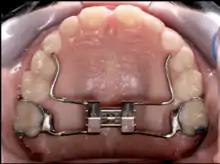

A palatal expander.